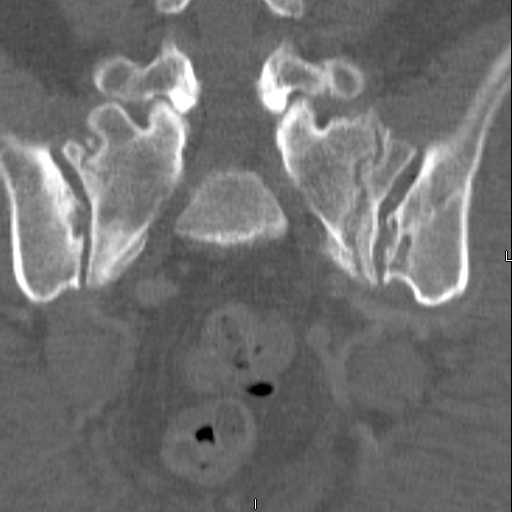

Here are a recent patient’s example slides...

3 Months After Fall

Continued Pain & Immobility

(+) Instability to Compressive Manual Exam

Pelvic CT Scan - 3 Months After Fall

Sacral Injuries

Ramus Fractures

Percutaneous Fixation

(B) Ramus-Retrograde

2 TransIliac-TransSacral

Upper Segment